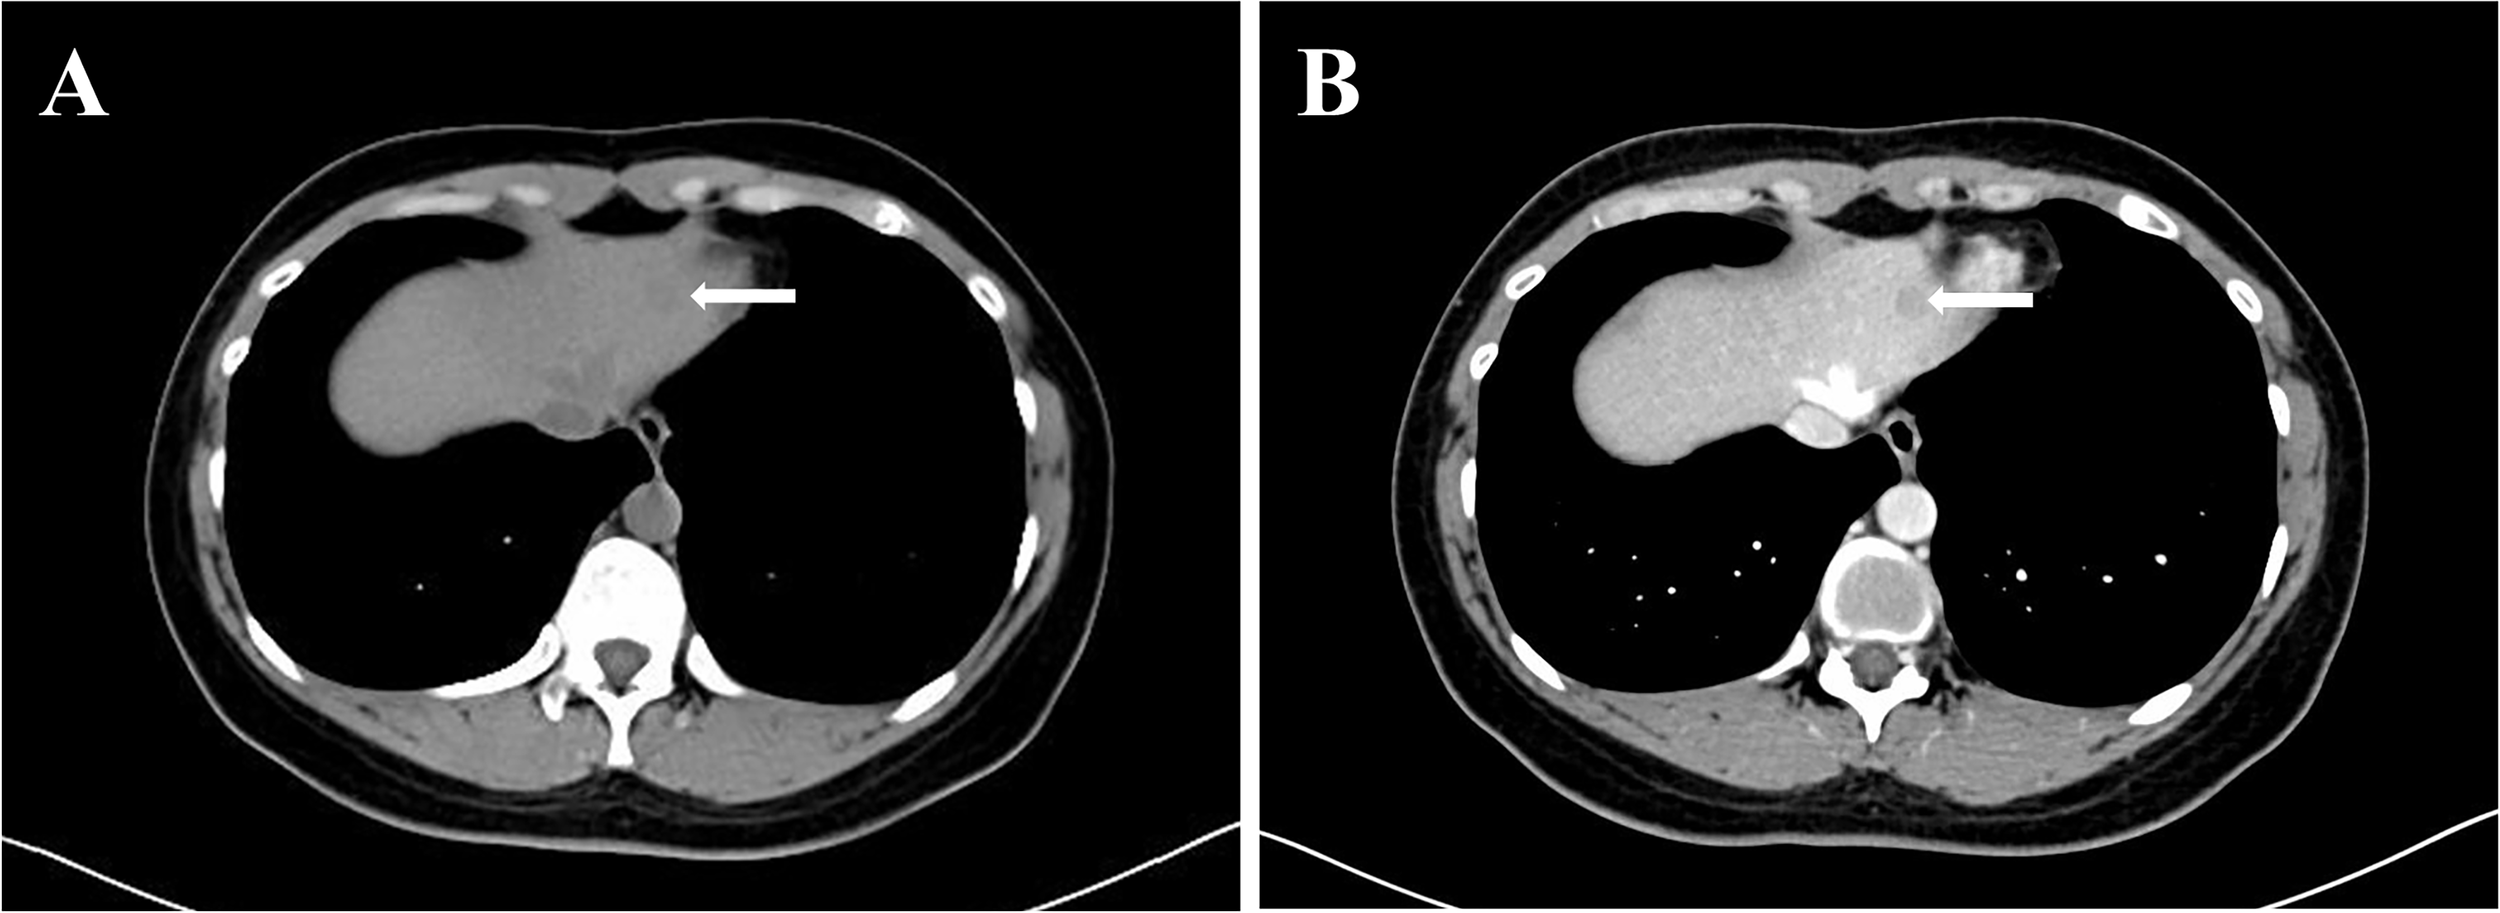

A 32-year-old Chinese female was admitted to Sichuan University West China Hospital with a 6-month history of upper abdominal pain. She denied previous radiotherapy or industrial chemical exposure. She had one previous pregnancy and and gave birth to a boy. In addition, she denied previous hormonal treatments and contraceptives. She was found to have viral hepatitis B for 6 years and had not received any treatment. Besides, she was healthy with no relevant medical or family history of diseases, such as hypertension or diabetes, and no history of smoking or alcohol consumption. Physical examination was unremarkable. A blood count showed Hb 14.2 g/dl (13–17.5), white blood cells 7.12×109/L (3.5-9.5), platelets 249×109/L (100–300), total bilirubin 12.5 umol/L (5.0-28), and AST 35 IU/L (<50). Serological testing for tumor marker of carcinoembryonic antigen (CEA) was 5.54 ng/ml (CEA ≥ 3.4 ng/ml was defined as abnormal) and hepatitis B surface antigen (HBsAg) was positive. The hepatitis B virus DNA (HBV-DNA) was less than 1×102 IU/ml (HBV-DNA ≥ 1×102 IU/ml was defined as HBV infection active), suggesting that HBV infection was inactive. The cancer antigen19-9 (CA19-9 ≥ 30 U/ml was defined as abnormal), CA125 (CA125 ≥ 24 U/ml was defined as abnormal) and α-fetoprotein (AFP≥ 7 ng/ml was defined as abnormal) was 25.6 U/ml, 13.3U/ml and 3.37, respectively. Abdominal computed tomography (CT) showed the lesion in the left lobe of liver was detected, and no tumor was detected in any other organs (Figure 1). Magnetic resonance imaging (MRI) of the upper abdomen was performed in our hospital for further diagnosis. The MRI showed a 1.1×1.3 cm lesion in the left lobe of liver, appearing low signal intensity on T1-weighted images and high signal intensity on T2-weighted images (Figure 2). Due to the similar appearance, hepatocellular carcinoma (HCC) was considered for preoperative diagnosis. The patient eventually underwent a laparoscopic liver resection of the left lobe. Macroscopically, the tumor was a yellowish solid mass with a diameter of 12mm. Microscopically, the lesion composed of undifferentiated epithelial cells with some atypical glands, and significant lymphocytic infiltration (Figure 3A). The epithelial tumor cells were featured by eosinophilic cytoplasm with large nuclei and prominent nucleoli. EBVencoded RNA (EBER) in situ hybridization was positive in tumor tissues. In addition, immunohistochemical analysis showed the lymphatic tissue positive for CD20 (B-cells, Figure 3B), CD3 (T-cells, Figure 3C), Ki-67 and negative for IgG4. Meanwhile, tumor cells positive for CK7 (Figure 3D), and negative for CK20, supporting the diagnosis of LEL-ICC.

FIGURE 2

Figure 2 Magnetic Resonance Imaging showed a 1.1×1.3 cm lesion in the left lobe of liver. (A) low signal intensity on T1-weighted images; (B) high signal intensity on T2-weighted images; (C) ring enhancing on DWI image; (D) ADC image of the lesion (ADC value: 800).